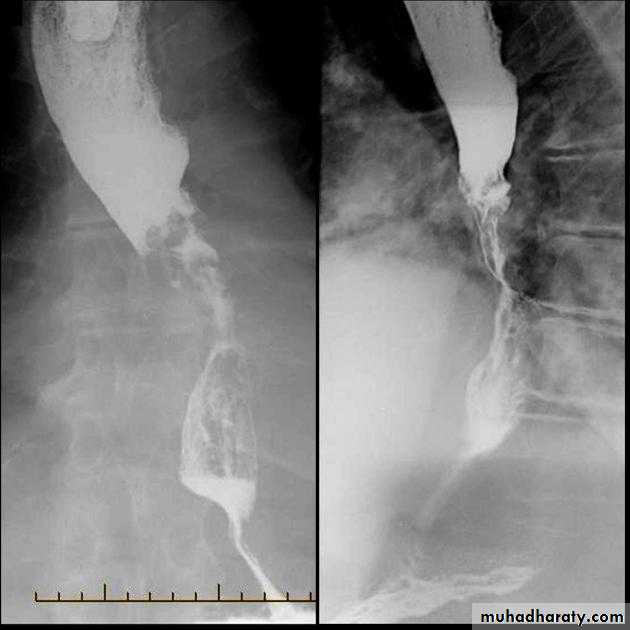

Esophageal diseases

Webs

Majority protrude from anterior esophageal wall

short, thin web (arrows) with minimal intraluminal extension.